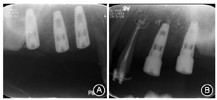

根分叉病变(furcation involvement,FI)3度,电活力测58,对照牙56。全口根尖X线片见图1,牙周检查表见图2。全口牙列不齐,上下前牙散在间隙,

粘接固定。牙周手术后3个月复查(图4),X线片显示

近中植骨区有高密度影形成(图5)。拆除